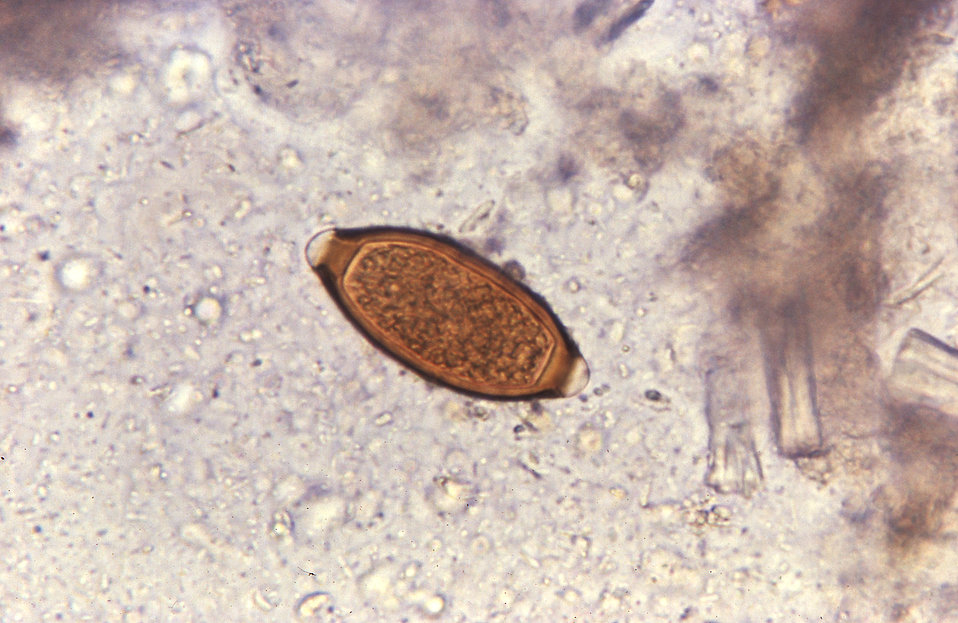

Фото 3. Трематоды.

Трематоду Описторхус по-другому называют двуусткой.

Ее брюшная присоска по виду напоминает ротовое отверстие. Гельминт поселяется в желчных протоках. Специфические симптомы — светлая окраска фекалий и сухость кожи. Продолжительность жизни паразита — многие годы.

Яйца трематоды выделяются с калом. Попадают в лужицы, где их проглатывают моллюски. Последние переползают в пруд или озеро. Личинка покидает моллюска и нападает на рыбу семейства карповых. Проникнув сквозь кожу, паразит поселяется в мышцах. Заражаются любители малосольной и копченой рыбы, изготовленной кустарным способом, а также их собаки.

Описторхус